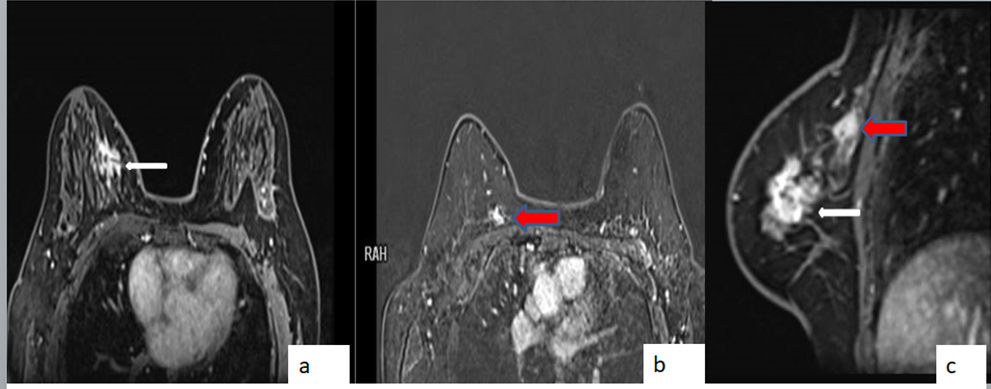

Figure 1- MLO (a) and CC (b) screening mammogram of the right breast with heterogeneous dense breast parenchyma shows a heterogeneous dense spiculate mass in lower inner quadrant (better seen on CC views; white arrow in figure 1b ). Figure 2 : Ultrasound shows a hypoechoic mass with spiculate margins, non parallel orientation and posterior acoustic shadowing. Figure 3: CEMRI reveals an irregular heterogeneous enhancing mass in lower inner quadrant (white arrow in figure 3a, c) and an additional small irregular heterogeneous enhancing mass in the upper inner quadrant (red arrow in image 3a, c) . Figure 4: Second look ultrasound revealed a hyperechoic mass with mild heterogeneity and indistinct margins which was not clearly appreciated with normal compression (figure 4a) and is better appreciated with excessive focal compression (figure 4b) . USG guided biopsy is performed as the mass was suspicious on CEMRI. Final histopathology for the second lesion - IDC